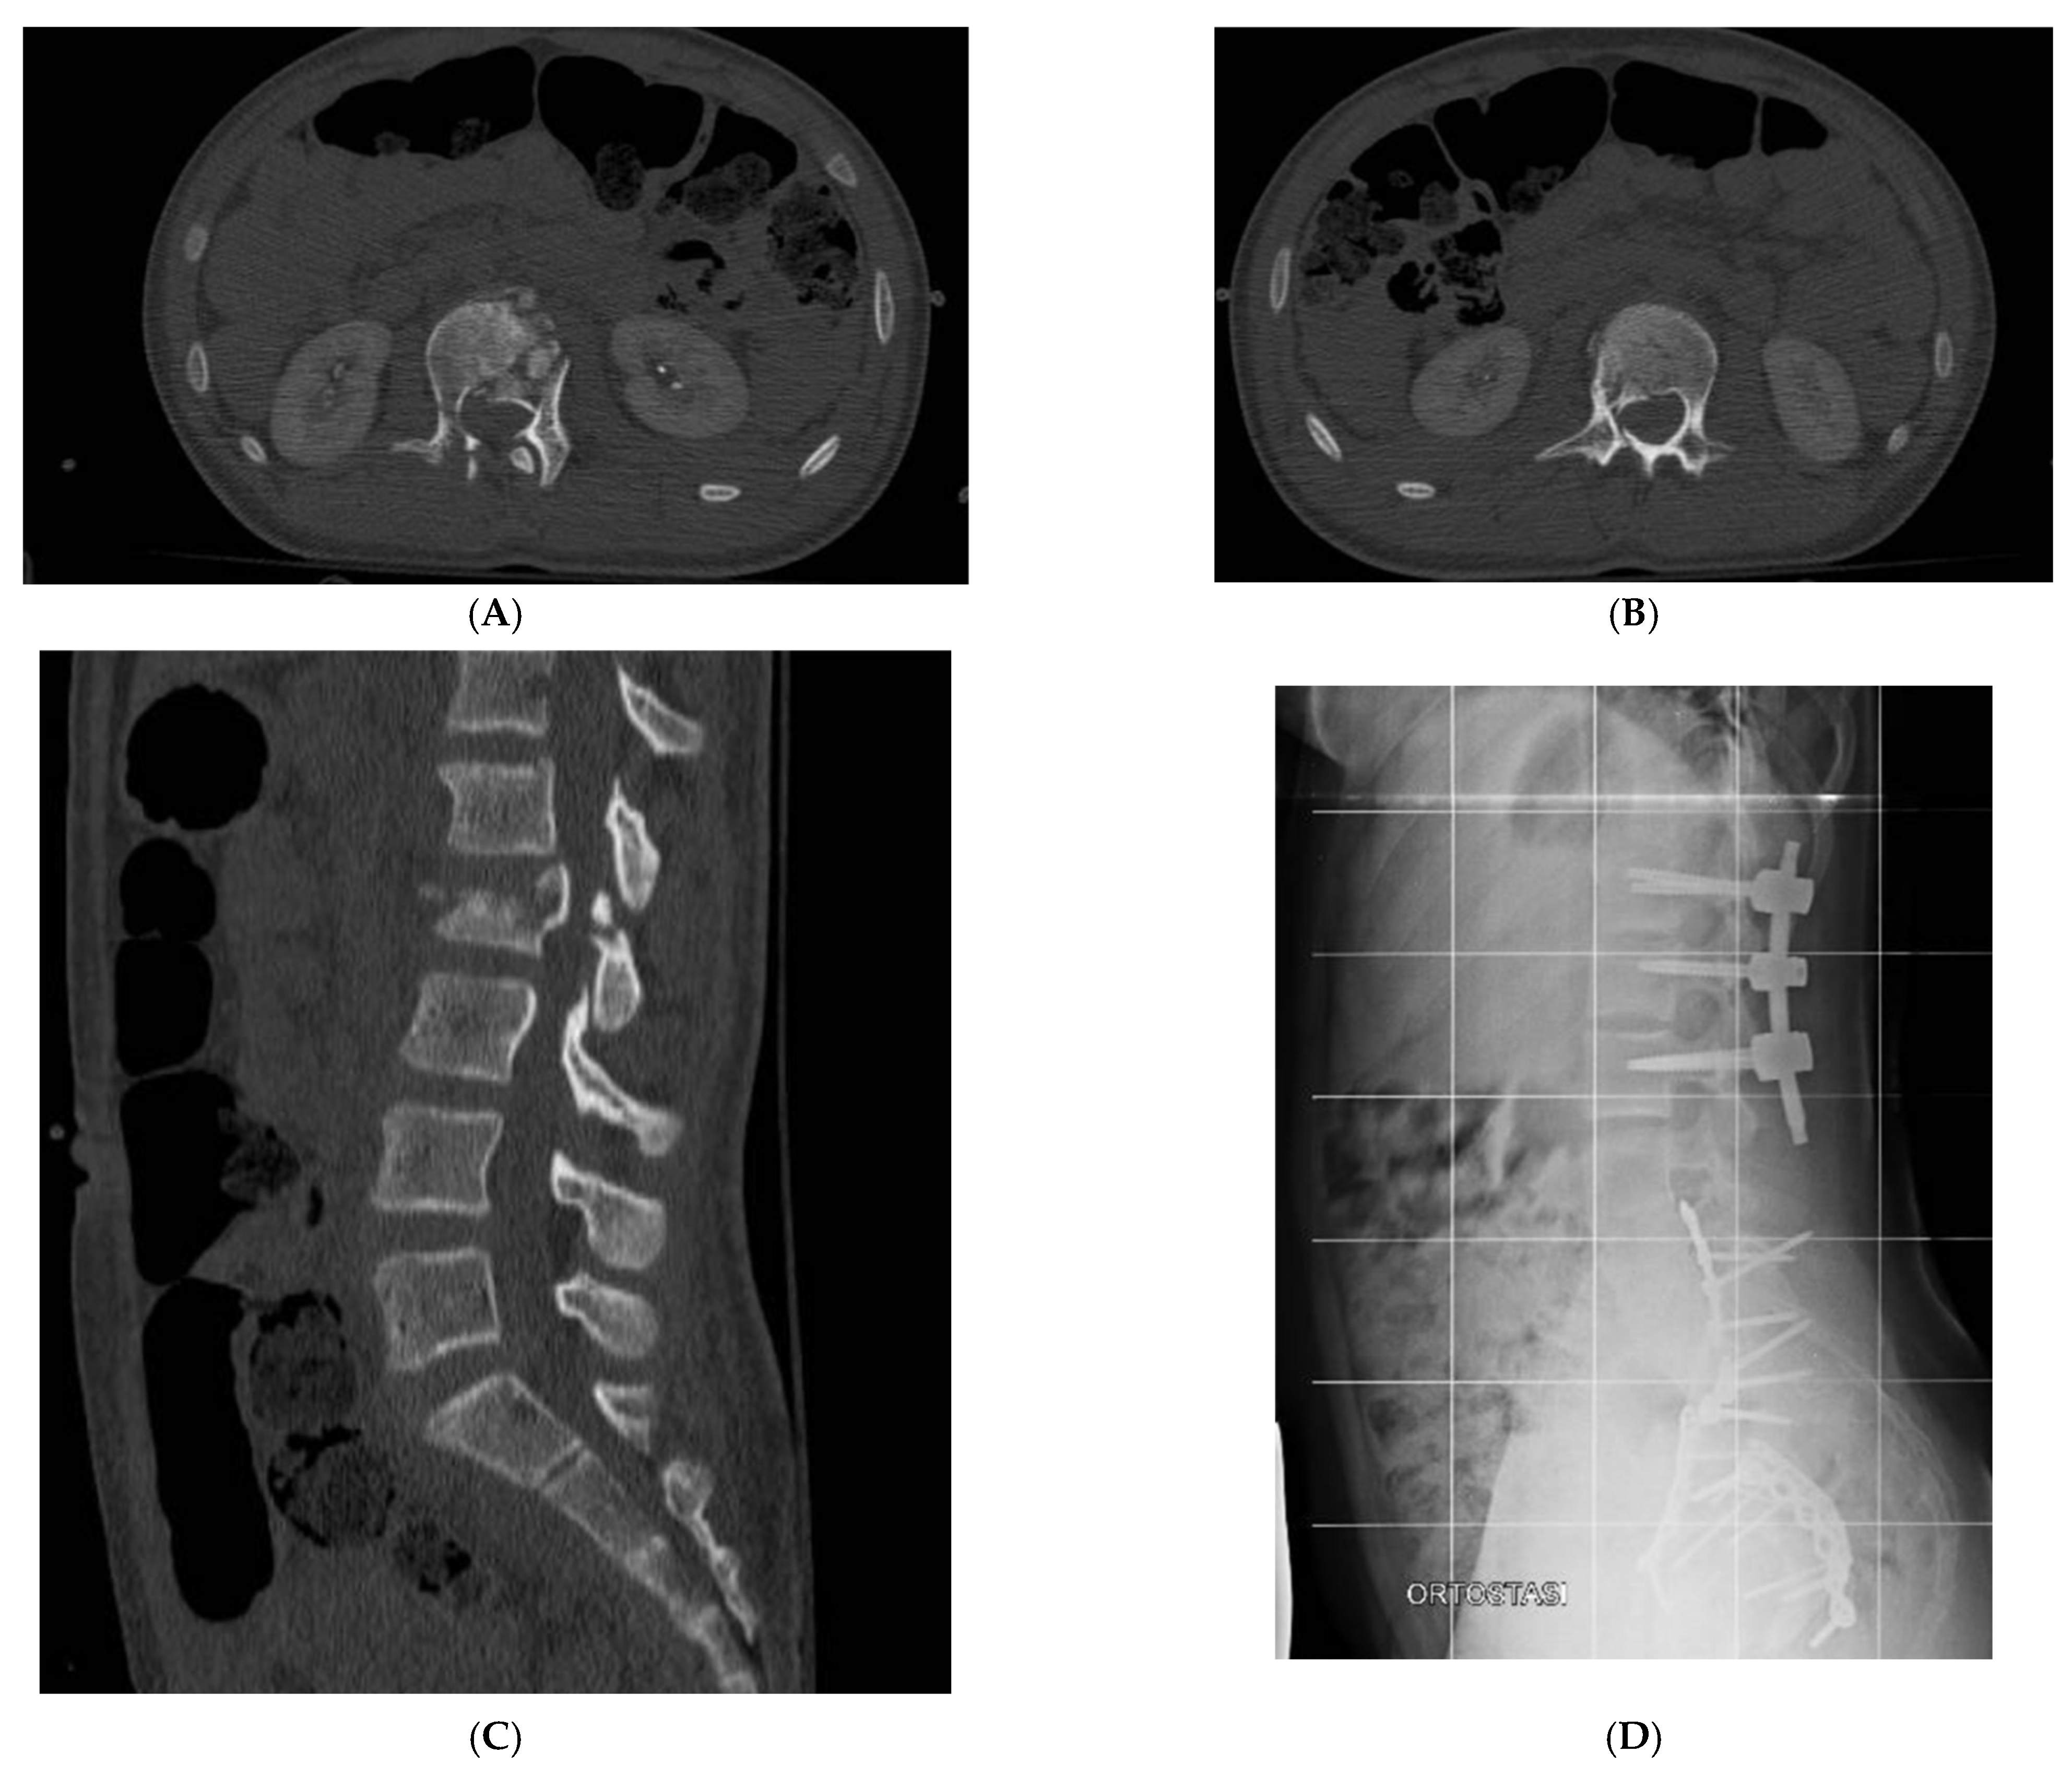

| 6 | L.G.G. | 10 y 5 m | F | C2 (AD 2), C5 (A4), C6 (A1), L1 (A1), L2 (A3), L3 (A0), L4 (A0), Right sacroiliac joint | multiple ribs, right acetabulum, ilio-ischiopubic bilateral branch, left heel | liver injury, splenic injury, pleural effusion | Halo-Vest and L1 to L3 Percutaneous pedicle fixation | 64 | 10 months No deficit |

| 7 | H.B. | 15 y 5 m | F | L5 (A0), Sacral U-Shaped Fracture (C3) | right acetabulum, bilateral olecranos, right femural shaft | paraplegia, complete neurogenic bowel and bladder dysfunction | L4 to Pelvis posterior open fusion, left sacral plate and L4 to S1 decompression | 30 | 8 months complete neurogenic bowel and bladder dysfunction; motor deficit of the right limb partial recovered |